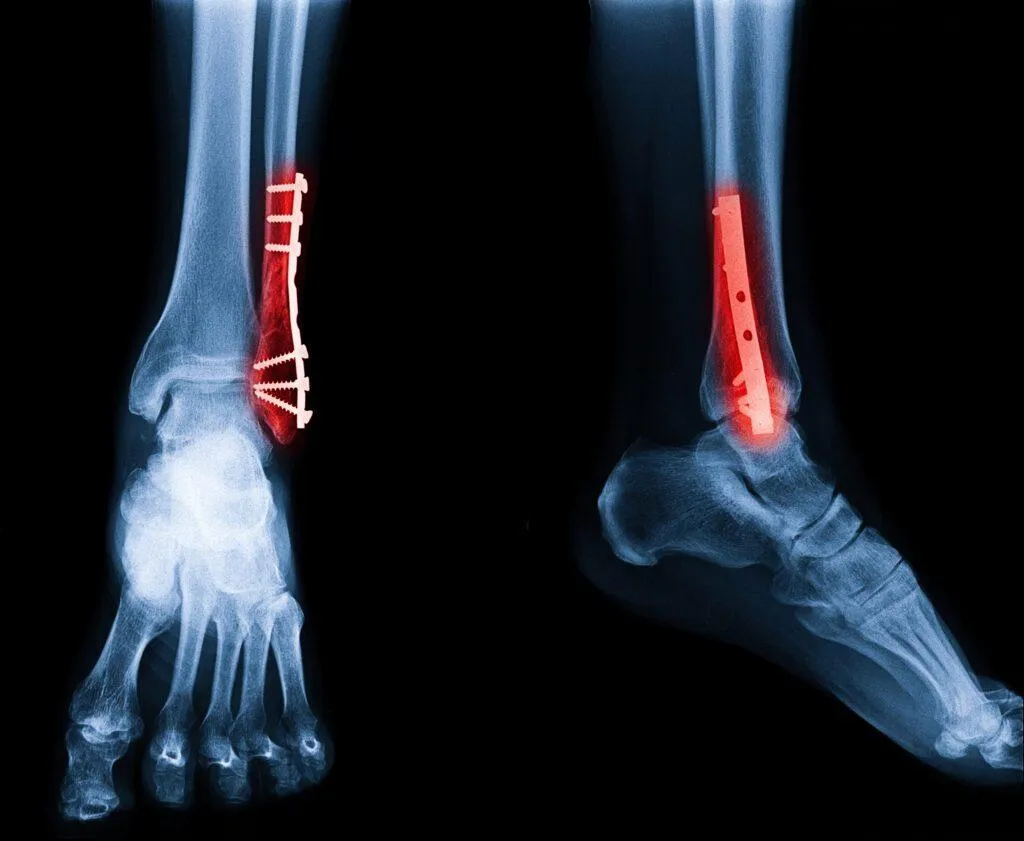

Ankle – Achilles repair, arthroscopy

Fractures